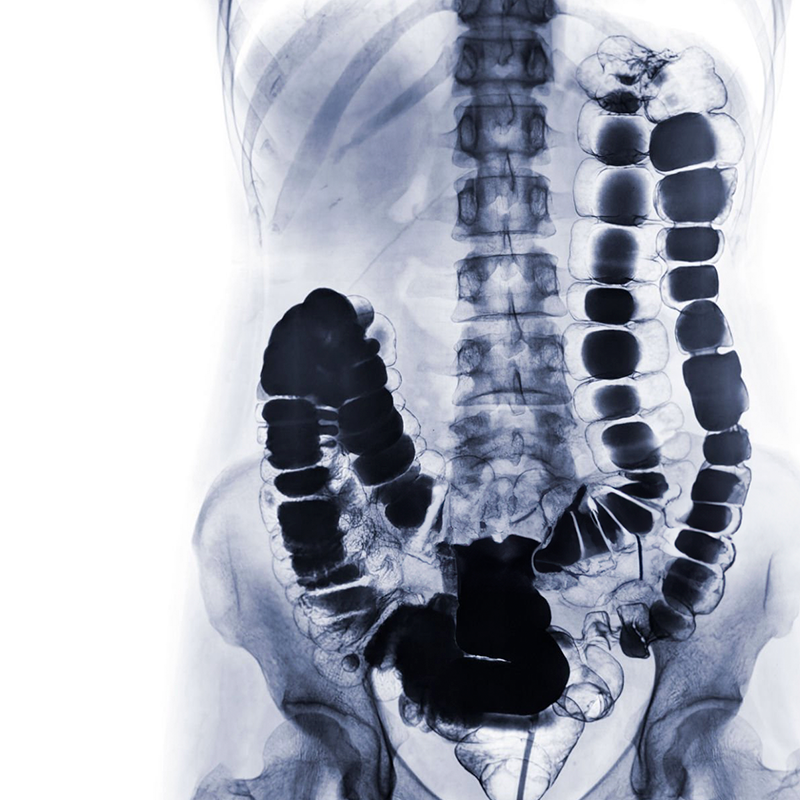

As radiografias convencionais com a utilização de meios de contrastes são exames de imagem realizados em clínicas e hospitais. O método utiliza radiografias e uso de equipamentos com videofluoroscopias, de modo rápido e preciso em muitos casos. O curso de Extensão em Radiografias Convencionais com Contraste – Exames Contrastados tem o objetivo de oferecer uma formação livre e completa na qual o professor apresenta a experiência profissional de forma didática e acessível à alunos e profissionais. O curso contempla as radiografias contrastadas gerais do corpo humano, tais como: sistema digestório (hipofaringe, esôfago, estômago e duodeno- REED, trânsito intestinal, enema opaco, defecograma; sistema urinário (urografia, pielografia, uretrocistografia masculina e feminina) glandulas e vias (Sialografia, colangiografia, dacriocistografia, histerossalpingografia), anatomia, fisiopatologia, elaboração de anamnese, posicionamentos do paciente e do equipamento, fatores de exposição, anatomia radiológica e oferece as dicas do professor aos alunos de forma que o aluno e o profissional da saúde desenvolva um raciocínio teórico e prático para o dia a dia.